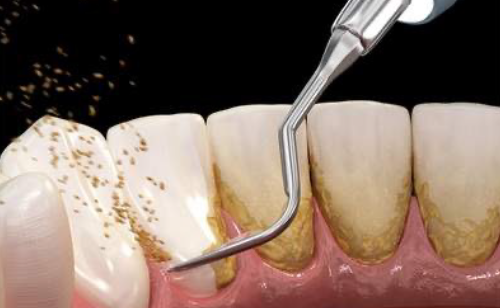

歯石除去・PMTC(着色と細菌膜の除去)

専用の器具とペーストを使い、できる限り低侵襲で歯の表面のバイオフィルムや着色を除去し見た目も綺麗で汚れの付きづらい状態へと仕上げます。歯の表面がツルツルになり爽快感も得られます。

| 治療に伴うリスク | ・歯茎の炎症が強いと歯石を取る際に出血することがあります ・処置後歯石がとれたことにより、歯がしみることがあります ・歯石がとれたり歯茎の炎症が引くことで、歯と歯の間に隙間ができ、息が漏れ発音しにくいと感じることがあります ・歯茎の炎症が軽減すると歯茎が引き締まり、歯が長く見えることがあります |

| 担当者所見 | 初診時は歯石が全顎的に付着しており、歯石除去時は出血もありました。特に下の前歯は歯と歯の間を埋めるように多量の歯石が付着していました。ブラッシング指導も行い、定期検診へと移行しました。 定期検診時は全体的な清掃状態も良好で、ご自身も歯ブラシを頑張っているとおっしゃっていました。矯正治療開始後も綺麗で健康な口腔内を維持する為、定期検診を継続的に行っていく予定です。 |